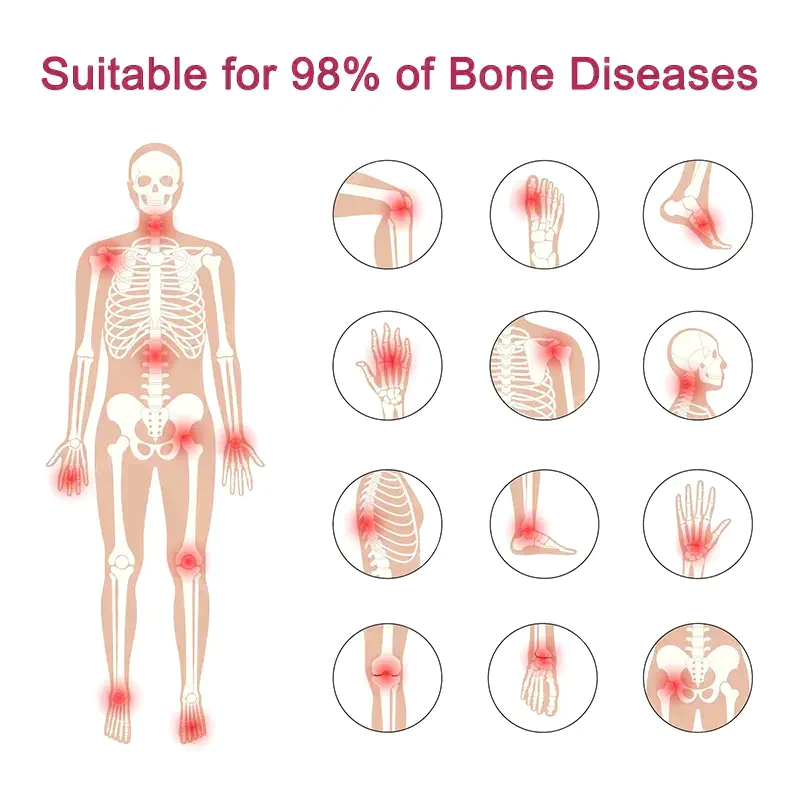

(u. a. Arthrose, rheumatoide Arthritis, Schleimbeutelentzündung, Sehnenentzündung, Osteoporose, Gicht, Karpaltunnelsyndrom, Bänderverstauchungen und -zerrungen, Ballenverformungen und Tennisarm).

Häufige orthopädische Gelenksymptome

Arthritis bezieht sich auf entzündliche Erkrankungen, die in den Gelenken und den umgebenden Geweben des menschlichen Körpers auftreten und durch Entzündung, Infektion, Degeneration, Trauma oder andere Faktoren verursacht werden, und kann in Dutzende von Arten unterteilt werden. Zu den klinischen Symptomen gehören Rötung, Schwellung, Hitze, Schmerzen, Funktionsstörungen und Verformungen der Gelenke, die zu einer Behinderung der Gelenke führen und die Lebensqualität der Patienten beeinträchtigen können.

Statistiken zufolge ist in den Vereinigten Staaten die Hälfte der Bevölkerung über 50 Jahre von Arthrose betroffen, 90 % der Frauen und 80 % der Männer über 65 Jahre. Die Lebenserwartung von Menschen mit schweren Symptomen verkürzt sich um etwa 10 bis 15 Jahre.

Gicht (metabolische Arthritis) wird durch einen Anstieg der Gichtbiosynthese, eine übermäßige Produktion von Harnsäure oder eine unzureichende Ausscheidung von Harnsäure verursacht, was zu einem Anstieg der Harnsäure im Blut führt und somit Gicht verursacht, die durch Hyperurikämie und wiederkehrende Episoden von akuter Gichtarthritis gekennzeichnet ist, die häufig in den Gelenken der großen Zehe, aber auch in den Gelenken der Hände, Knie, Ellenbogen usw. auftritt.

Oveallgo™ Gelenk- und Knochentherapie-Creme ist bekannt für seine Wirksamkeit bei der Behandlung eines breiten Spektrums orthopädischer Probleme.